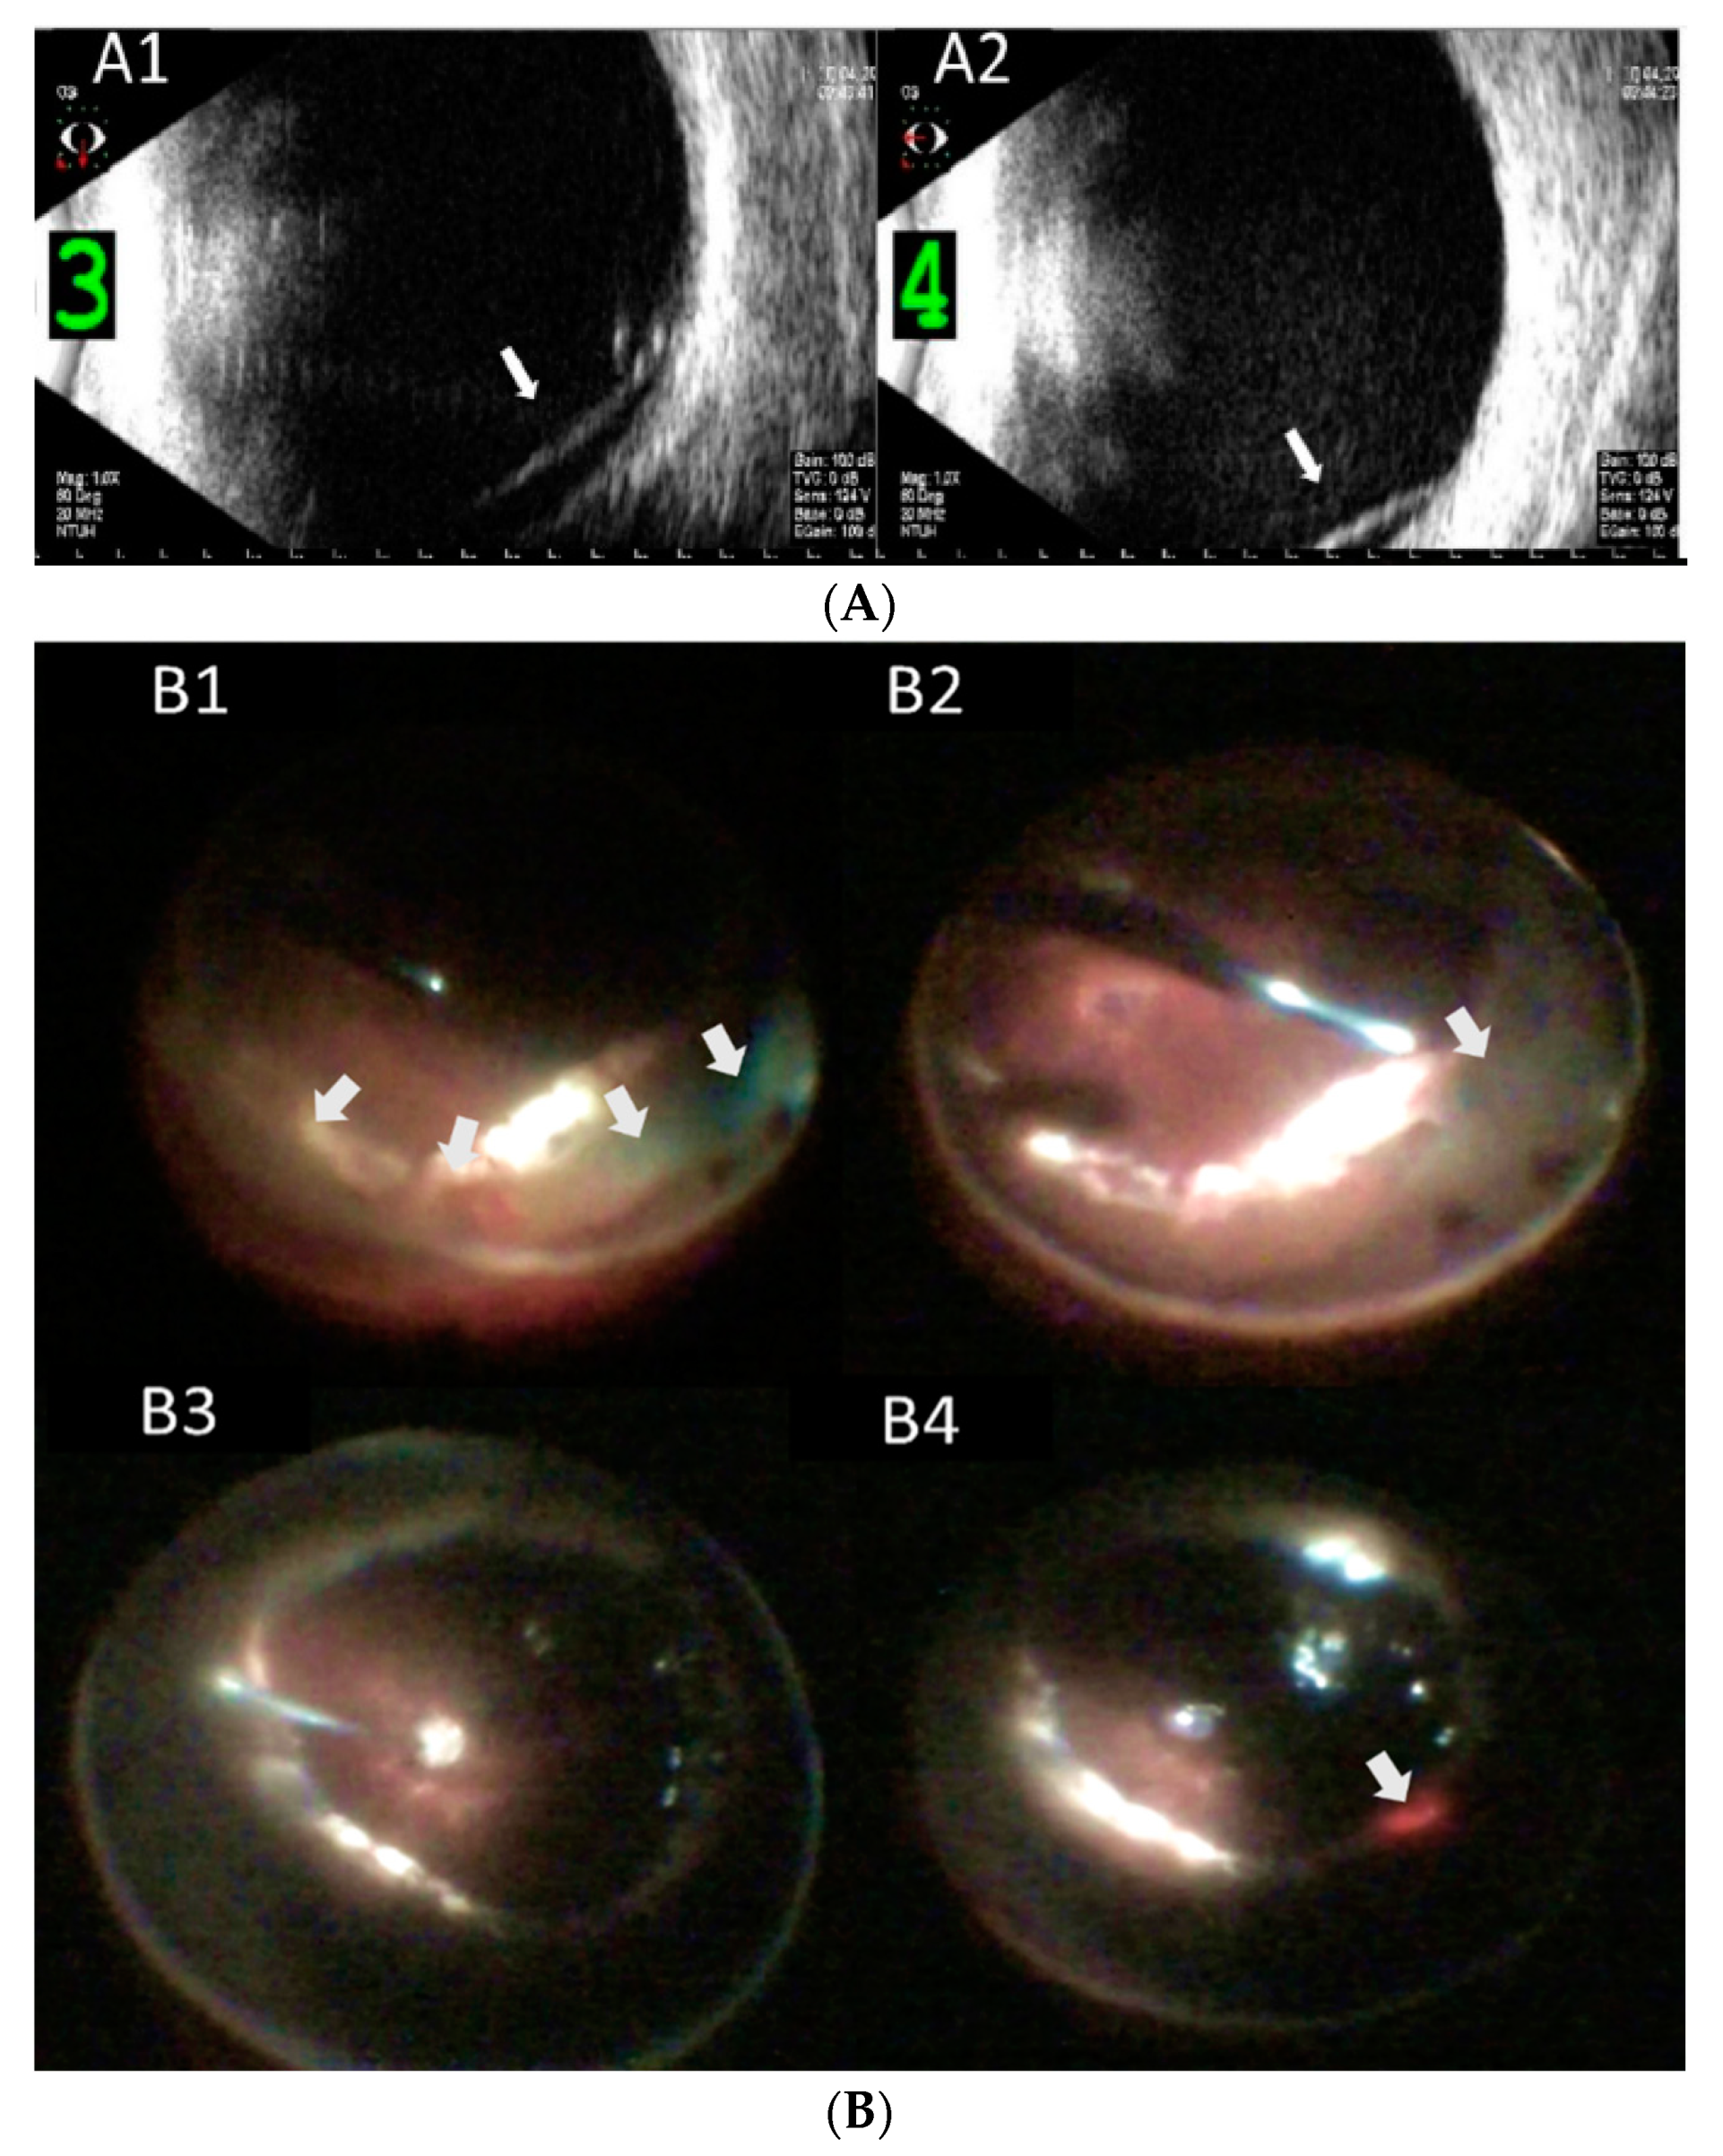

| 3 | 46 | M | R | 0.05 (1.3) | 39 | - | + | - | PPV*2, SB + SO + PPL | Aphakia | 26 | 270° retinectomy + SO refill | 225° pRD | + | 6 | 0.1 (1.0) | WNL | |

| 4 | 40 | M | R | 0.025 (1.6) | WNL | - | + | - | PPV*1, SB + SO + PPL | Aphakia | 22 | 180° retinectomy + PI + SO refill | 180° pRD | - | 22 | 0.05 (1.3) | WNL | |